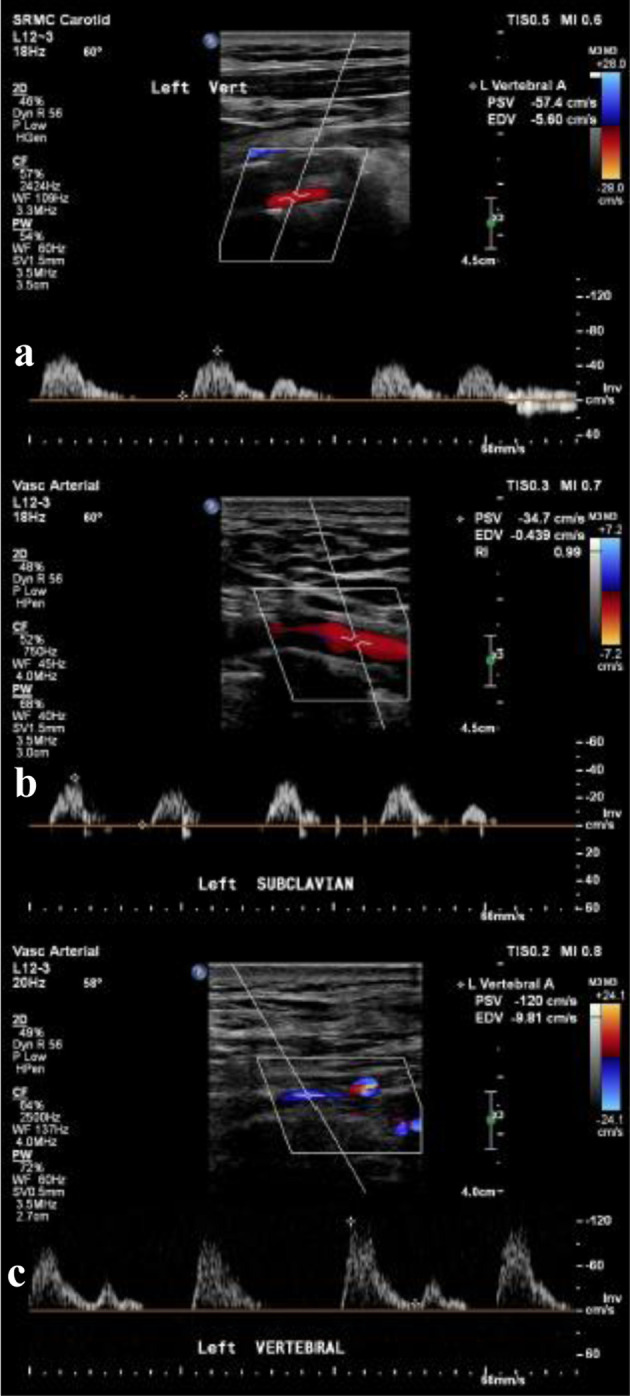

The subclavian steal syndrome (SSS) is defined by the reversal of flow in the ipsilateral vertebral artery in the setting of subclavian artery stenosis proximal to its origin. Here, we describe a rare case of left SSS with significant left subclavian artery stenosis associated with anomalous origin of the left vertebral artery (LVA) directly from the aortic arch in a patient presenting with signs of vertebrobasilar insufficiency and resolution of symptoms following angioplasty. Through this case, the authors try to emphasize the importance and the correct technique of using Doppler ultrasonography, and the importance of invasive angiography in understanding the mechanism of subclavian steal in patients with anomalous LVA origin.